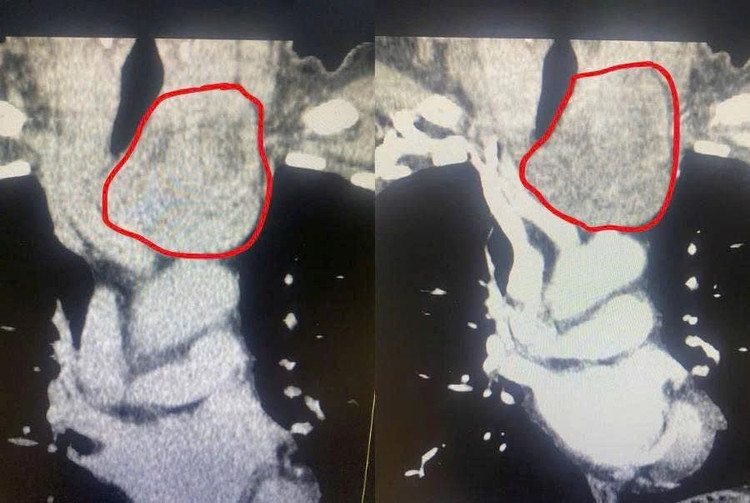

Qua thăm khám và thực hiện các cận lâm sàng, chẩn đoán hình ảnh CT cho thấy: Khối u tuyến giáp kích thước lớn, thòng xuống trung thất trước, gây chèn ép đẩy lệch khí quản.

Hình ảnh u tuyến giáp thòng xuống trung thất, chèn ép khí quản - Ảnh BVCC